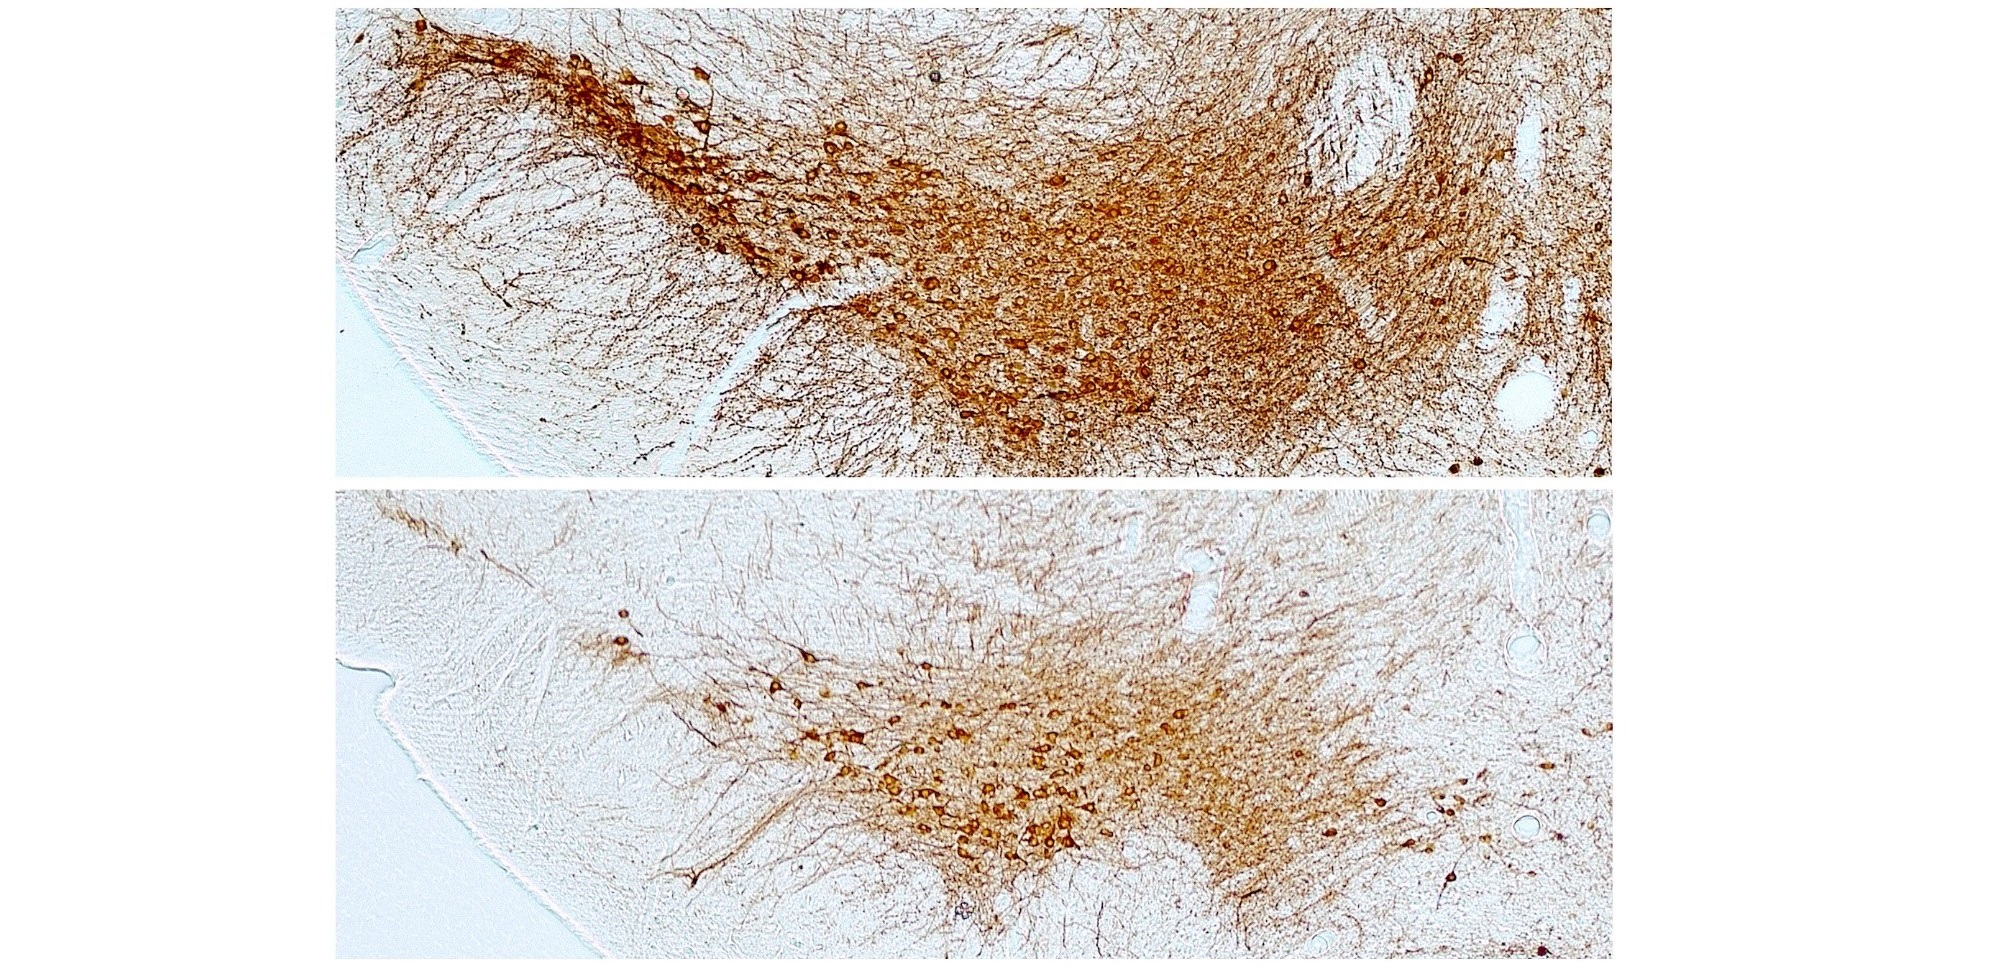

Identifican cambios en la estructura cerebral relacionados con las alteraciones cognitivas y de comportamiento en ELA